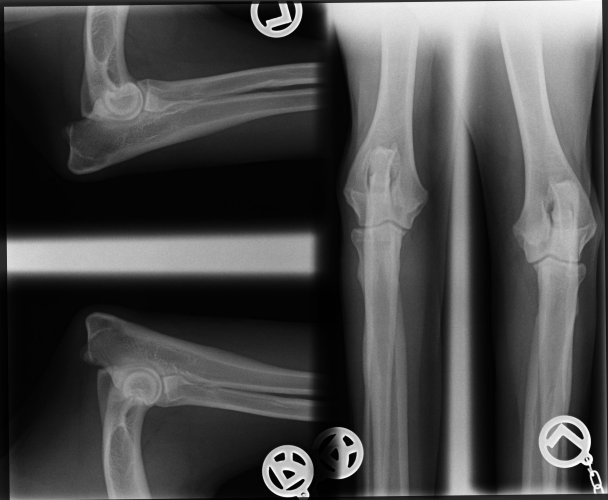

geb.1.12.2012, HD und ED frei

ED Befund